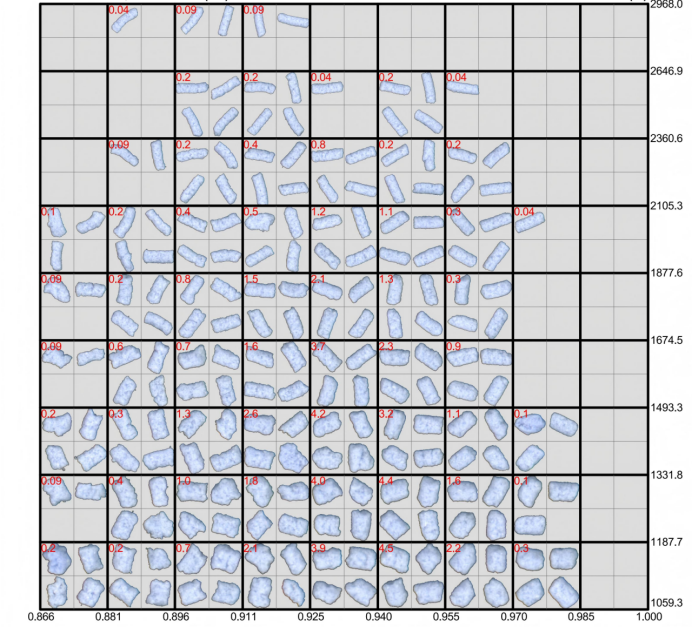

5.大視野測量:ZMS850配備了大面積的光學掃描平臺,單次掃描即可覆蓋直徑達100mm的樣品,能夠同時捕捉上千個微丸顆粒的圖像信息。

二、蔗糖丸芯檢測:精準把控 “制劑基底” 質量

蔗糖丸芯是緩釋、控釋微丸制劑的常用載體,其粒徑均一性與圓整度直接影響后續藥物包衣的均勻性,某批次蔗糖丸芯的檢測數據如下(可參考):

2. 形貌特征:圓整度優異,滿足包衣需求

三、擠出劑微丸檢測:助力 “成型工藝” 優化

擠出劑微丸由藥物與輔料經擠出 - 滾圓工藝制成,其粒徑與形貌直接影響藥物溶出速率。以某擠出劑微丸為例,ZMS850 的檢測數據為工藝優化提供了依據(可參考):